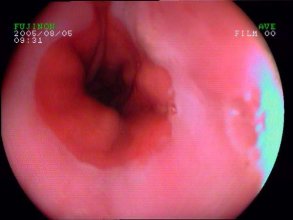

食管炎即食道炎,泛指食管黏膜浅层或深层组织由于受到刺激或损伤,食管黏膜发生水肿和充血而引发的炎症。化学性刺激包括胃酸、胆汁、烈酒以及强酸、强碱、药物等;物理性刺激包括烫的食物、食管异物(鱼刺等)嵌顿,长期放置鼻胃管等。由于化学治疗、放射治疗导致食管局部受损,或患者本身抵抗力下降导致结核杆菌、真菌(念珠菌)或病毒感染亦可引发食管炎。临床最常见的是胃酸反流引起的反流性食管炎。